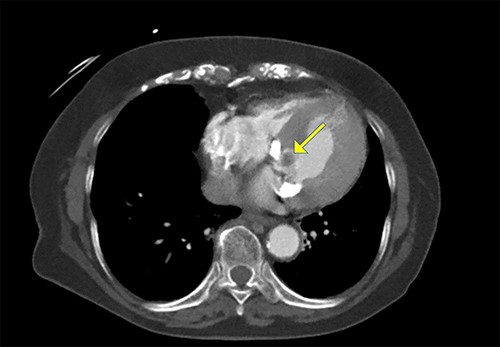

An 86-year-old woman with a history of hypertension and hyperlipidemia presented to our hospital with episodes of syncope lasting several minutes. On admission, her consciousness was clear, and there were no significant neurological findings on physical examination. Electrocardiography showed sinus rhythm at 79 bpm. Laboratory findings showed no abnormalities in electrolytes or anemia that could cause syncope. The coronary angiogram showed 90% stenosis of the right coronary artery (RCA). Transthoracic echocardiography (TTE) and transesophageal echocardiography (TEE) both showed a mobile mass with a maximum diameter of 12 mm on the anterior annulus of the mitral valve (Figs 1 and 2). TTE showed normal left ventricle (LV) function with an ejection fraction of 60%, LV wall motion was within the normal range and no significant valvular disease was detected. Preoperative chest computed tomography showed severe mitral annular calcification (MAC) (Fig. 3).

Cardiac computed tomography showing a cardiac mass in the mitral annulus with heavy mitral annular calcification.